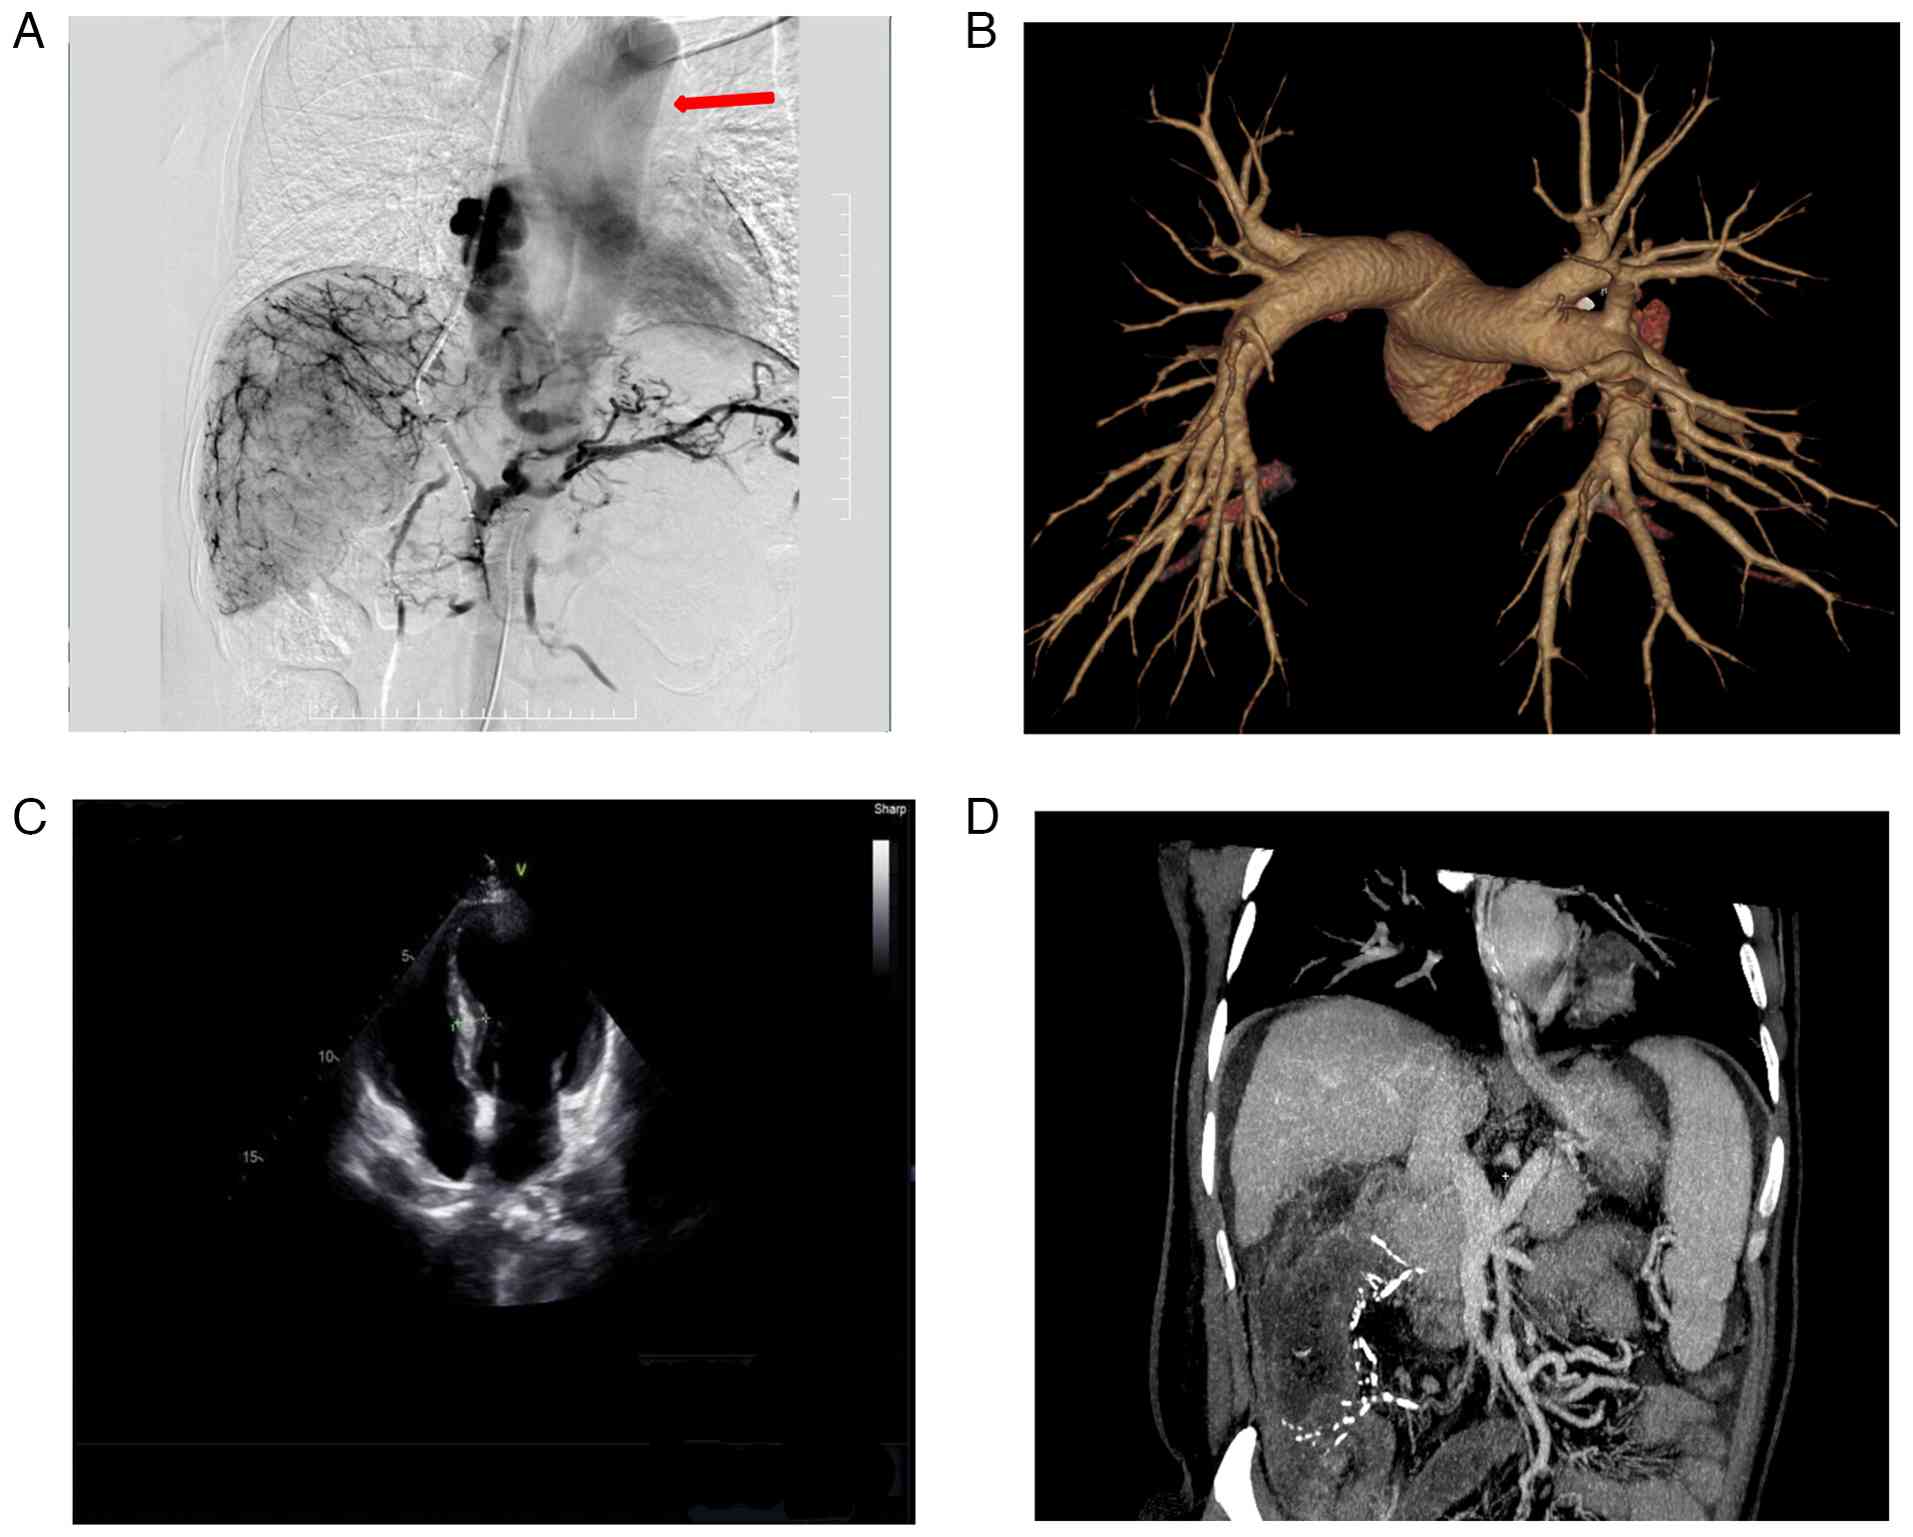

To identify the embolic source, further evaluation was conducted. Echocardiography excluded patent foramen ovale or intracardiac thrombus (Fig. 2C). Additionally, no arteriovenous malformations or pulmonary embolism was found on pulmonary CT angiography (Fig. 2B).

Intraoperative angiography

demonstrated direct drainage from the esophageal variceal plexus to

the left heart and ascending aorta, exclusion of conventional

shunts and underlying abdominal pathology. (A) Sequential

fluoroscopic images obtained during the procedure reveal the

abnormal vascular pathway in this single patient. Contrast medium

injected into the esophageal variceal plexus drains directly into

the left heart and subsequently fills the ascending aorta

(indicated by arrows), completely bypassing the pulmonary

circulation. This rare anatomical variant provided the direct

conduit for the embolic material to enter the systemic arterial

circulation. (B) Pulmonary CT angiography shows no evidence of

pulmonary arteriovenous malformations or pulmonary embolism, ruling

out intrapulmonary shunting. (C) Echocardiography reveals normal

cardiac chambers with no signs of patent foramen ovale or

intracardiac thrombus, excluding intracardiac shunting sources. (D)

Contrast-enhanced abdominal CT scan demonstrates marked

splenomegaly, extensive esophageal varices and ascites, confirming

the background of decompensated cirrhosis and portal

hypertension.

Figure 2

Intraoperative angiography demonstrated direct drainage from the esophageal variceal plexus to the left heart and ascending aorta, exclusion of conventional shunts and underlying abdominal pathology. (A) Sequential fluoroscopic images obtained during the procedure reveal the abnormal vascular pathway in this single patient. Contrast medium injected into the esophageal variceal plexus drains directly into the left heart and subsequently fills the ascending aorta (indicated by arrows), completely bypassing the pulmonary circulation. This rare anatomical variant provided the direct conduit for the embolic material to enter the systemic arterial circulation. (B) Pulmonary CT angiography shows no evidence of pulmonary arteriovenous malformations or pulmonary embolism, ruling out intrapulmonary shunting. (C) Echocardiography reveals normal cardiac chambers with no signs of patent foramen ovale or intracardiac thrombus, excluding intracardiac shunting sources. (D) Contrast-enhanced abdominal CT scan demonstrates marked splenomegaly, extensive esophageal varices and ascites, confirming the background of decompensated cirrhosis and portal hypertension.

Notably, retrospective analysis of fluoroscopic angiography demonstrated direct drainage from the esophageal variceal plexus to the left atrium and ascending aorta, bypassing the pulmonary circulation (Fig. 2A and D and Video S1). This anatomical variant likely accounted for the cerebral embolism.